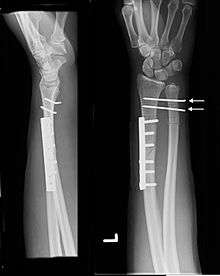

![]() Galeazzi fracture. Arrow points at the dislocated ulnar head | |

The Galeazzi fracture is a fracture of the radius with dislocation of the distal radioulnar joint. It classically involves an isolated fracture of the junction of the distal third and middle third of the radius with associated subluxation or dislocation of the distal radio-ulnar joint; the injury disrupts the forearm axis joint.[1]

Galeazzi fractures are best treated with open reduction of the radius and the distal radio-ulnar joint.[2] It has been called the "fracture of necessity," because it necessitates open surgical treatment in the adult. Nonsurgical treatment results in persistent or recurrent dislocations of the distal ulna.[1] However, in skeletally immature patients such as children, the fracture is typically treated with closed reduction.[1]